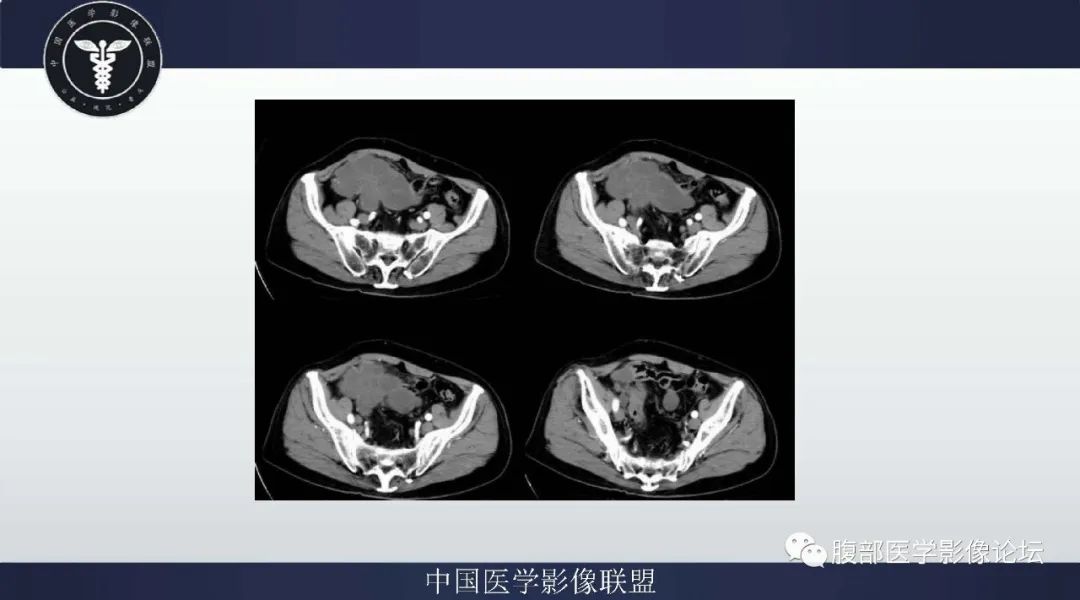

李广明:定位腹腔,肿块CT密度低,t2明显高信号 考虑含有粘液基质,有点状钙化,肿块与肠管分界不清,阑尾显示不清,病灶上方有少量气体影,临床cea高,考虑恶性,阑尾来源粘液腺癌首先考虑。鉴别粘液性脂肪肉瘤,此病例与阑尾关系密切,暂不首先考虑。 医学百科网 | YxBaike.Com

邱勇刚:老年男性,回盲部病灶,阑尾显示不清,T2这么亮,部分管道状结构,临床CEA升高,支持首先考虑阑尾粘液腺癌。

纳木错:右中下腹盆占位,与肠系膜,阑尾分界不清,T1低,T2高提示内含粘液,增强后实性部分、分隔及囊壁延迟强化,CEA升高,考虑来源于阑尾的黏液腺癌。

向前向后:病灶沿肠系膜包绕血管生长,囊性部分较多,边缘强化,定位应该是肠系膜粘液血管型不排除;淋巴瘤,包绕血管;粘液腺瘤做鉴别。 医学百科网 | YxBaike.Com